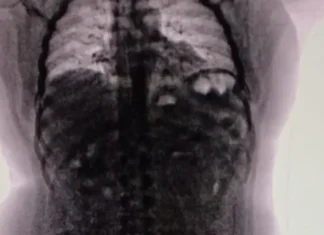

Cayó un narcotraficante con 90 cápsulas de cocaína en su cuerpo

El hombre, oriundo de Perú, estuvo cuatro días hospitalizado hasta que pudo expulsar todos los recipientes que cargaba en su tracto digestivo